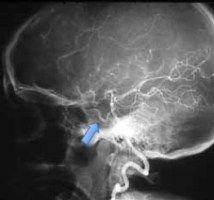

l’artère basilaire

elle naît de la réunion des 2 artères vertébrales en avant de la jonction bulbo-protubérantielle. elle donnes des collatérales principales (cérébelleuses moyennes, auditives internes), des branches perforantes circonférentielles courtes et longues, et se termine en 4 branches formant un X : les cérébelleuses supérieures et cérébrales postérieures, entre ces artères passent les nerfs oculo-moteurs.

lors de l’engagement, la terminaison du tronc basilaire peut être plicaturée, donnant une ischémie croisée : de la cérébrale postérieure homolatérale et cérébelleuse supérieure contro-latérale.